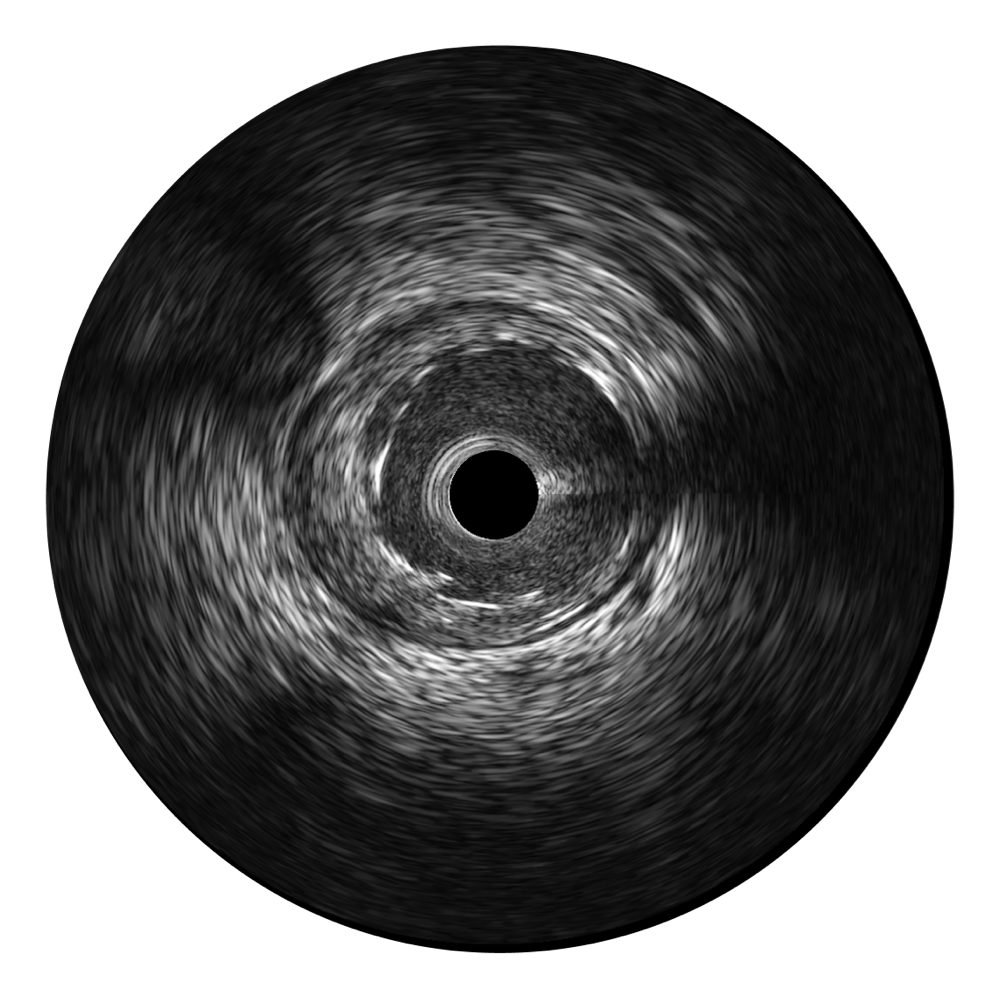

开立宽频IVUS图像

传统IVUS图像

对比传统IVUS导管成像,开立宽频IVUS图像的近场支架梁显影更细腻,远场中膜外血管仍清晰可辨,兼顾远中近,兼顾分辨力与穿透深度